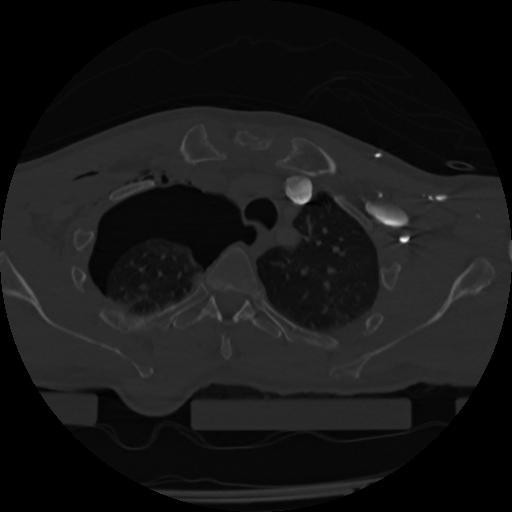

22 ANGIO,CE,Vol,0.5,ANGIO,,